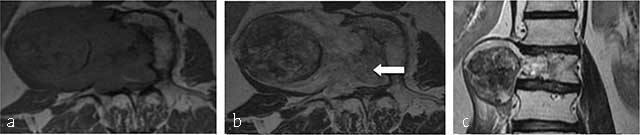

Figure 3

Chondrosarcoma of C7. (a) Lateral radiograph of cervical spine shows a large iuxta-osseous calcified mass arising from the vertebral body of C7 (arrow). (b, c, d, e) MR: Sagittal T1-WI, Sagittal T2-WI, Transversal T1-WI, Transversal T1-WI after gadolinium contrast injection show lobulated mass of intermediate signal intensity on T1-WI and high signal intensity on T2-WI (arrows) with ring-and-arc enhancement (arrowhead).